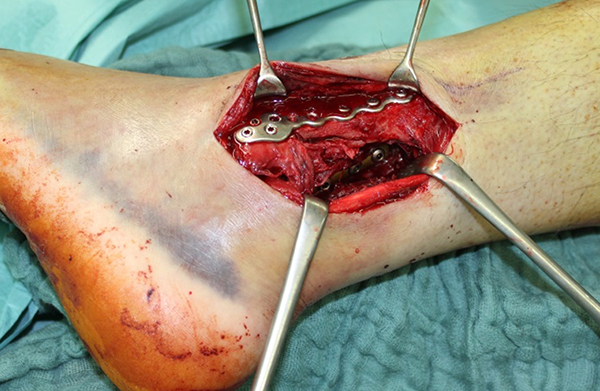

Die Versorgung von AO 44-B Frakturen erfolgt über einen längsverlaufenden lateralen Zugang. In der Regel gelingt eine suffiziente Stabilisierung mittels interfragmentärer Zugschraube (bei langem Frakturverlauf ggf. 2 Zugschrauben) und einer zusätzlichen Neutralisationsplatte (Abbildung 9 & 10).

Bei multifragmentären Frakturen (AO 44-B2.3) oder bei schlechter Knochenqualität sollte die Versorgung mittels winkelstabiler Plattenosteosynthese erwogen werden (Abbildung 11 & 12).

Gardner et al. konnten beispielsweise zeigen, dass die offene anatomische Reposition der Tibiahinterkante der Stabilisierung mittels Stellschraube überlegen war und gleichzeitig mit einer geringeren Rate an postoperativen Fehlstellungen der Fibula in der CT-Kontrolle einherging 2728. Aus Sicht der Autoren ist prinzipiell die Stabilisierung über eine direkte Reposition indiziert, wenn die Größe des Fragmentes dies erlaubt. Bei gleichzeitigem Vorliegen einer Fraktur des lateralen und/oder medialen Malleolus sollte zunächst die Versorgung der des Tibiahinterkantenfragments erfolgen. Dies erlaubt die radiologische Kontrolle der Reposition und Osteosynthese-Lage, welche durch eine zuvor aufgebrachte Fibula-Platte häufig erschwert ist 29. Dafür werden die Patienten in Seitenlage gelagert. Dies erlaubt die direkte Versorgung der posterioren Malleolusfraktur über einen posterolateralen Zugang 30. Das sehr kräftige Periost wird im Frakturverlauf inzidiert und aus den Frakturspalt entfernt, so kann eine anatomische Reposition erfolgen. Entsprechend der Fragmentgröße erfolgt entweder die Versorgung mittels Drittelrohrplatte in Antiglide-Technik oder eine Zugschraubenosteosynthese. Die Versorgung der Fibula-Fraktur gelingt über den gleichen Zugang. Zur Versorgung des medialen Malleolus wird der Patient auf den Rücken umgelagert. Dies kann bei entsprechender Vorbereitung ohne erneutes steriles Abdecken erfolgen. Durch dieses Vorgehen konnte im eigenen Kollektiv die Notwendigkeit einer Stabilisierung der Syndesmose mit Stellschraube/Tight Rope deutlich reduziert werden.